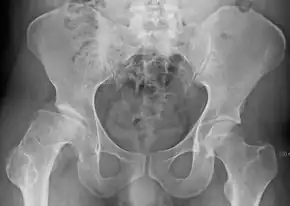

![]() | |

| Radiograph of a person with Legg–Calvé–Perthes disease | |